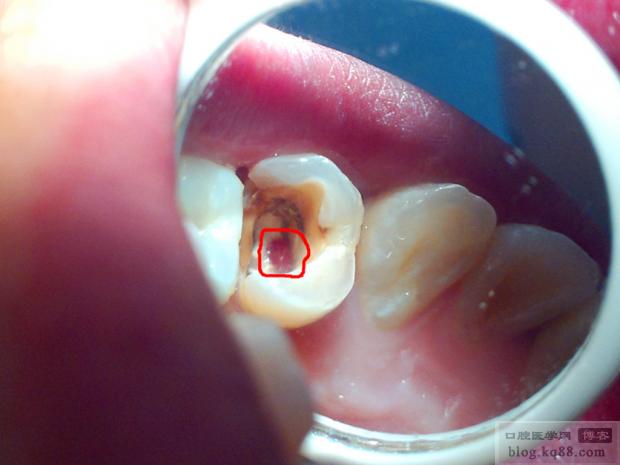

根管侧穿是指在进行根管治疗或根管预备过程中,器械意外穿出根管壁,导致根管与牙周组织之间形成异常通道,这是一个并发症,但并非无法补救,及时、正确的处理是保存患牙的关键。

- 精确放置: 在显微镜下操作,确保材料仅覆盖穿孔区域,避免进入根管或牙周间隙,使用专用输送器(如MTA输送器、Biodentine注射器)。

(图片来源网络,侵删)完成根管充填后,按照常规进行牙体修复(桩核+全冠),恢复牙齿外形和功能,防止牙折。

(图片来源网络,侵删) -